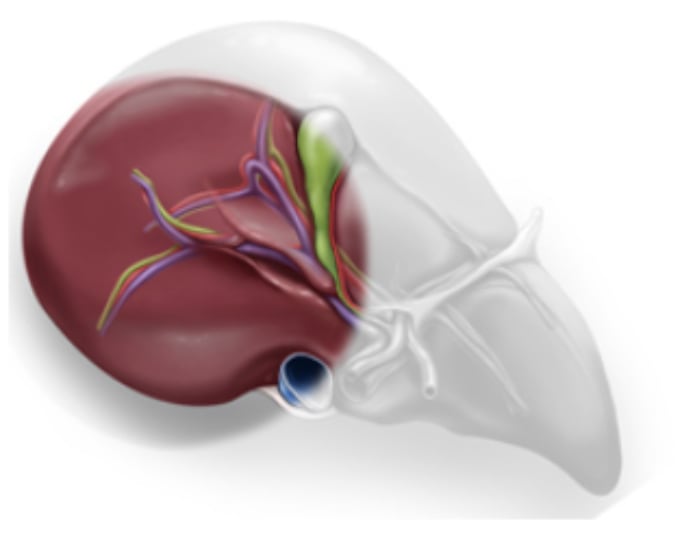

The right hepatic vein is higher than the vena cava: P (right hepatic vein) < P(vena cava)